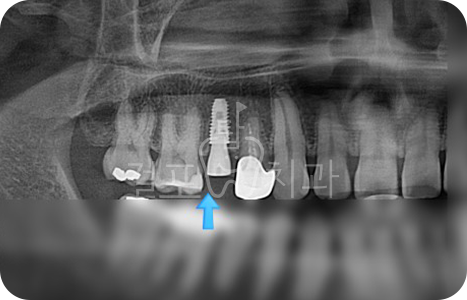

• 치아 파절로 내원하신 분입니다. 잇몸뼈가 튼튼하신 분으로 발치즉시 임플란트가 가능하였습니다.

Before

After

• 치아 뽑은 자리 잇몸염증이 매우 심한 상태였습니다. 잇몸상태가 좋지 않아도

발치 즉시 임플란트를 시도할 수 있습니다. 다만, 2~3달 지난 후 수술한다면 더 안전하므로 이런 경우 즉시 식립을 추천드리지 않습니다. 발치 몇 달 후 상악동 거상술과 뼈이식 임플란트를 함께하여 수술을 완료하였습니다.